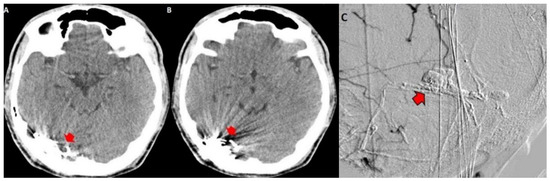

3.2. Imaging Studies